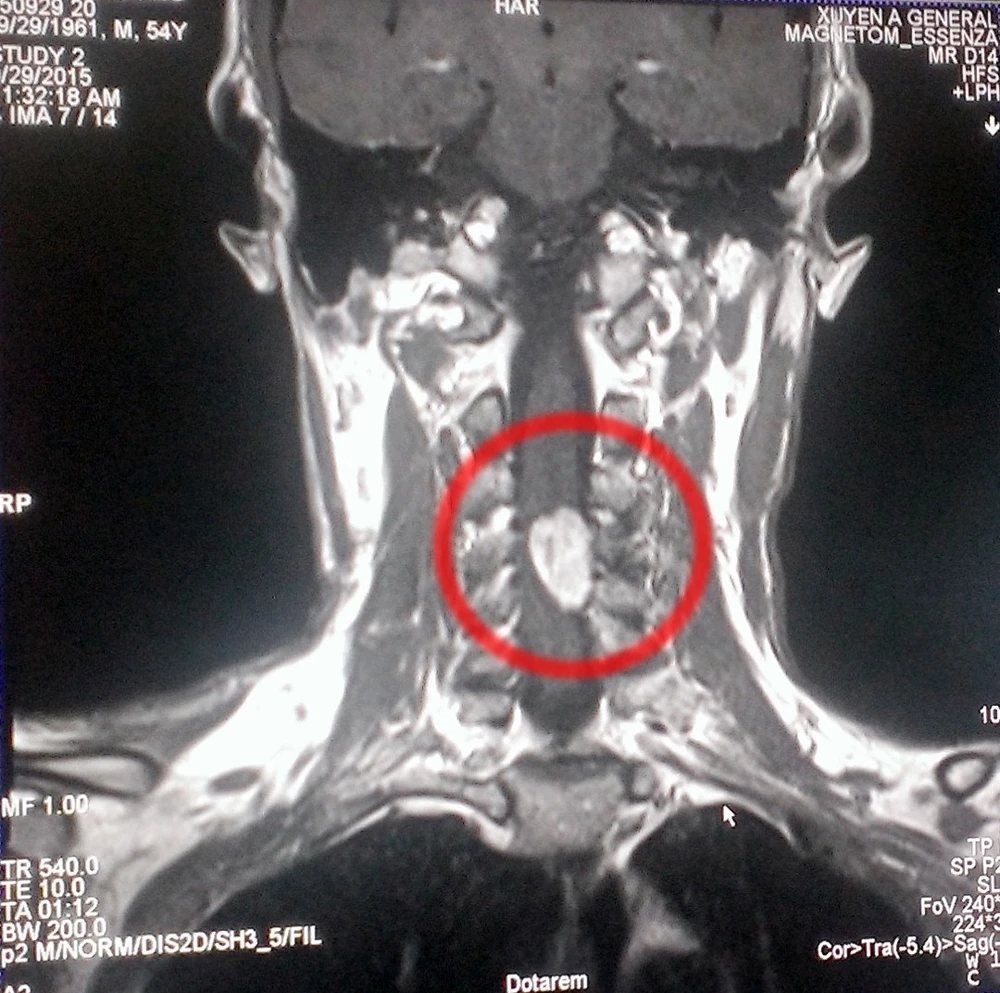

Khối u trong tủy của bệnh nhân LVC (54 tuổi, xã Thanh Tuyền, huyện Dầu Tiếng, tỉnh Bình Dương).

Kết quả hình chụp MRI cho thấy bệnh nhân có u sao bào thân sống, u màng ống nội tủy. Có thương tổn thoát vị đĩa đệm đốt C3/C4, C4/C5, C5/C6 hai bên, khả năng chèn ép đường đi của rễ thần kinh C5 bên phải. Các bác sĩ Ngoại Thần kinh đã phối hợp hội chẩn và phẫu thuật, sau đó tiến hành vi phẫu lấy từng phần u, bóc tách u khỏi tủy sống, cắt các sợi thần kinh dính chặt vào thân u.

“U tủy chèn ép trên 90% tủy sống, bệnh nhân sắp vào giai đoạn liệt tứ chi. Cần phải phẫu thuật u tủy sống, nếu không sẽ dẫn đến liệt tứ chi”, BS Đinh Văn Cội cho biết.